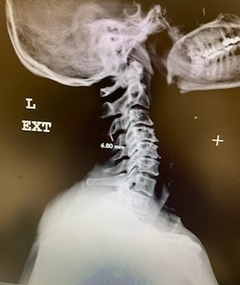

(2b) Lateral Flexion cervical x-rays extension image demonstrating 8mm of splaying of the C34 interspinous distance.

(3) Post operative AP and lateral cervical x-ray demonstrating good placement of hardware and alignment.

Patient did well from surgery with reduced pain in left shoulder and no further leak.(Fig. 3)